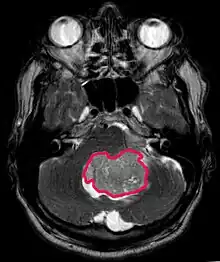

Este tumor é típico da fossa posterior, onde se localiza em ambos os hemisférios do cerebelo ou no vermis cerebelar. Por ser invasivo e de crescimento rápido, geralmente se espalha para outras partes do sistema nervoso central (SNC) através do LCR e pode se infiltrar no assoalho do quarto ventrículo próximo e nas meninges. Mais raramente, podem ocorrer metástases adicionais no SNC. Quando a malignidade ocorre, os sintomas incluem perda de equilíbrio, incoordenação, diplopia, disartria e devido ao envolvimento do quarto ventrículo, que muitas vezes resulta em hidrocefalia obstrutiva, cefaleia, náuseas e vômitos e marcha instável.

A ressonância magnética geralmente mostra uma lesão maciça com realce de contraste envolvendo o cerebelo. Como mencionado acima, o meduloblastoma tem alta propensão a infiltrar localmente as leptomeninges, bem como a se espalhar pelo espaço subaracnóideo, envolvendo os ventrículos, a convexidade cerebral e as superfícies leptomeníngeas da coluna. Consequentemente, é necessário trazer todo o eixo cranioespinhal em ressonância.

O objetivo da cirurgia é remover o máximo possível da massa apresentada pela lesão. De fato, os tumores residuais pós-operatórios resultam em pior prognóstico. Também um prenúncio de um prognóstico desfavorável é a presença de células tumorais no líquido cefalorraquidiano ou a detecção por ressonância de metástases leptomeníngeas. A cirurgia por si só geralmente não é curativa. Em alguns casos, no entanto, pode ocorrer irradiação terapêutica do eixo cranioespinhal, focada no local do tumor primário. A adição de quimioterapia após a radioterapia aumenta a taxa de cura. Medicamentos à base de platina (cisplatina ou carboplatina), etoposídeo e um agente alquilante (ciclofosfamida ou lomustina) são usados com vincristina. Com tratamento adequado, casos de longa sobrevida de mais de 3 anos em pacientes com meduloblastoma variam de 60 a 60 anos e 80 Por cento.